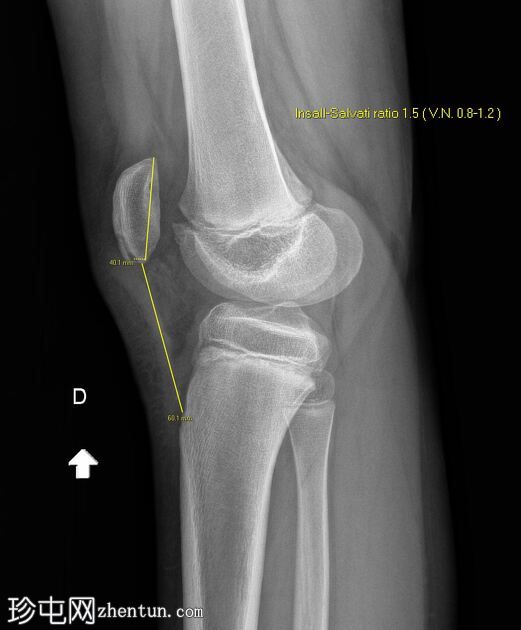

放大

正位

4.jpeg

侧位

5.jpeg

髌骨下极可见一小块薄骨碎片,伴有髌骨高位,Insall-Salvati比值为1.5(V.N. 0.8 - 1.2)。膝前可见软组织肿胀。左膝正常。